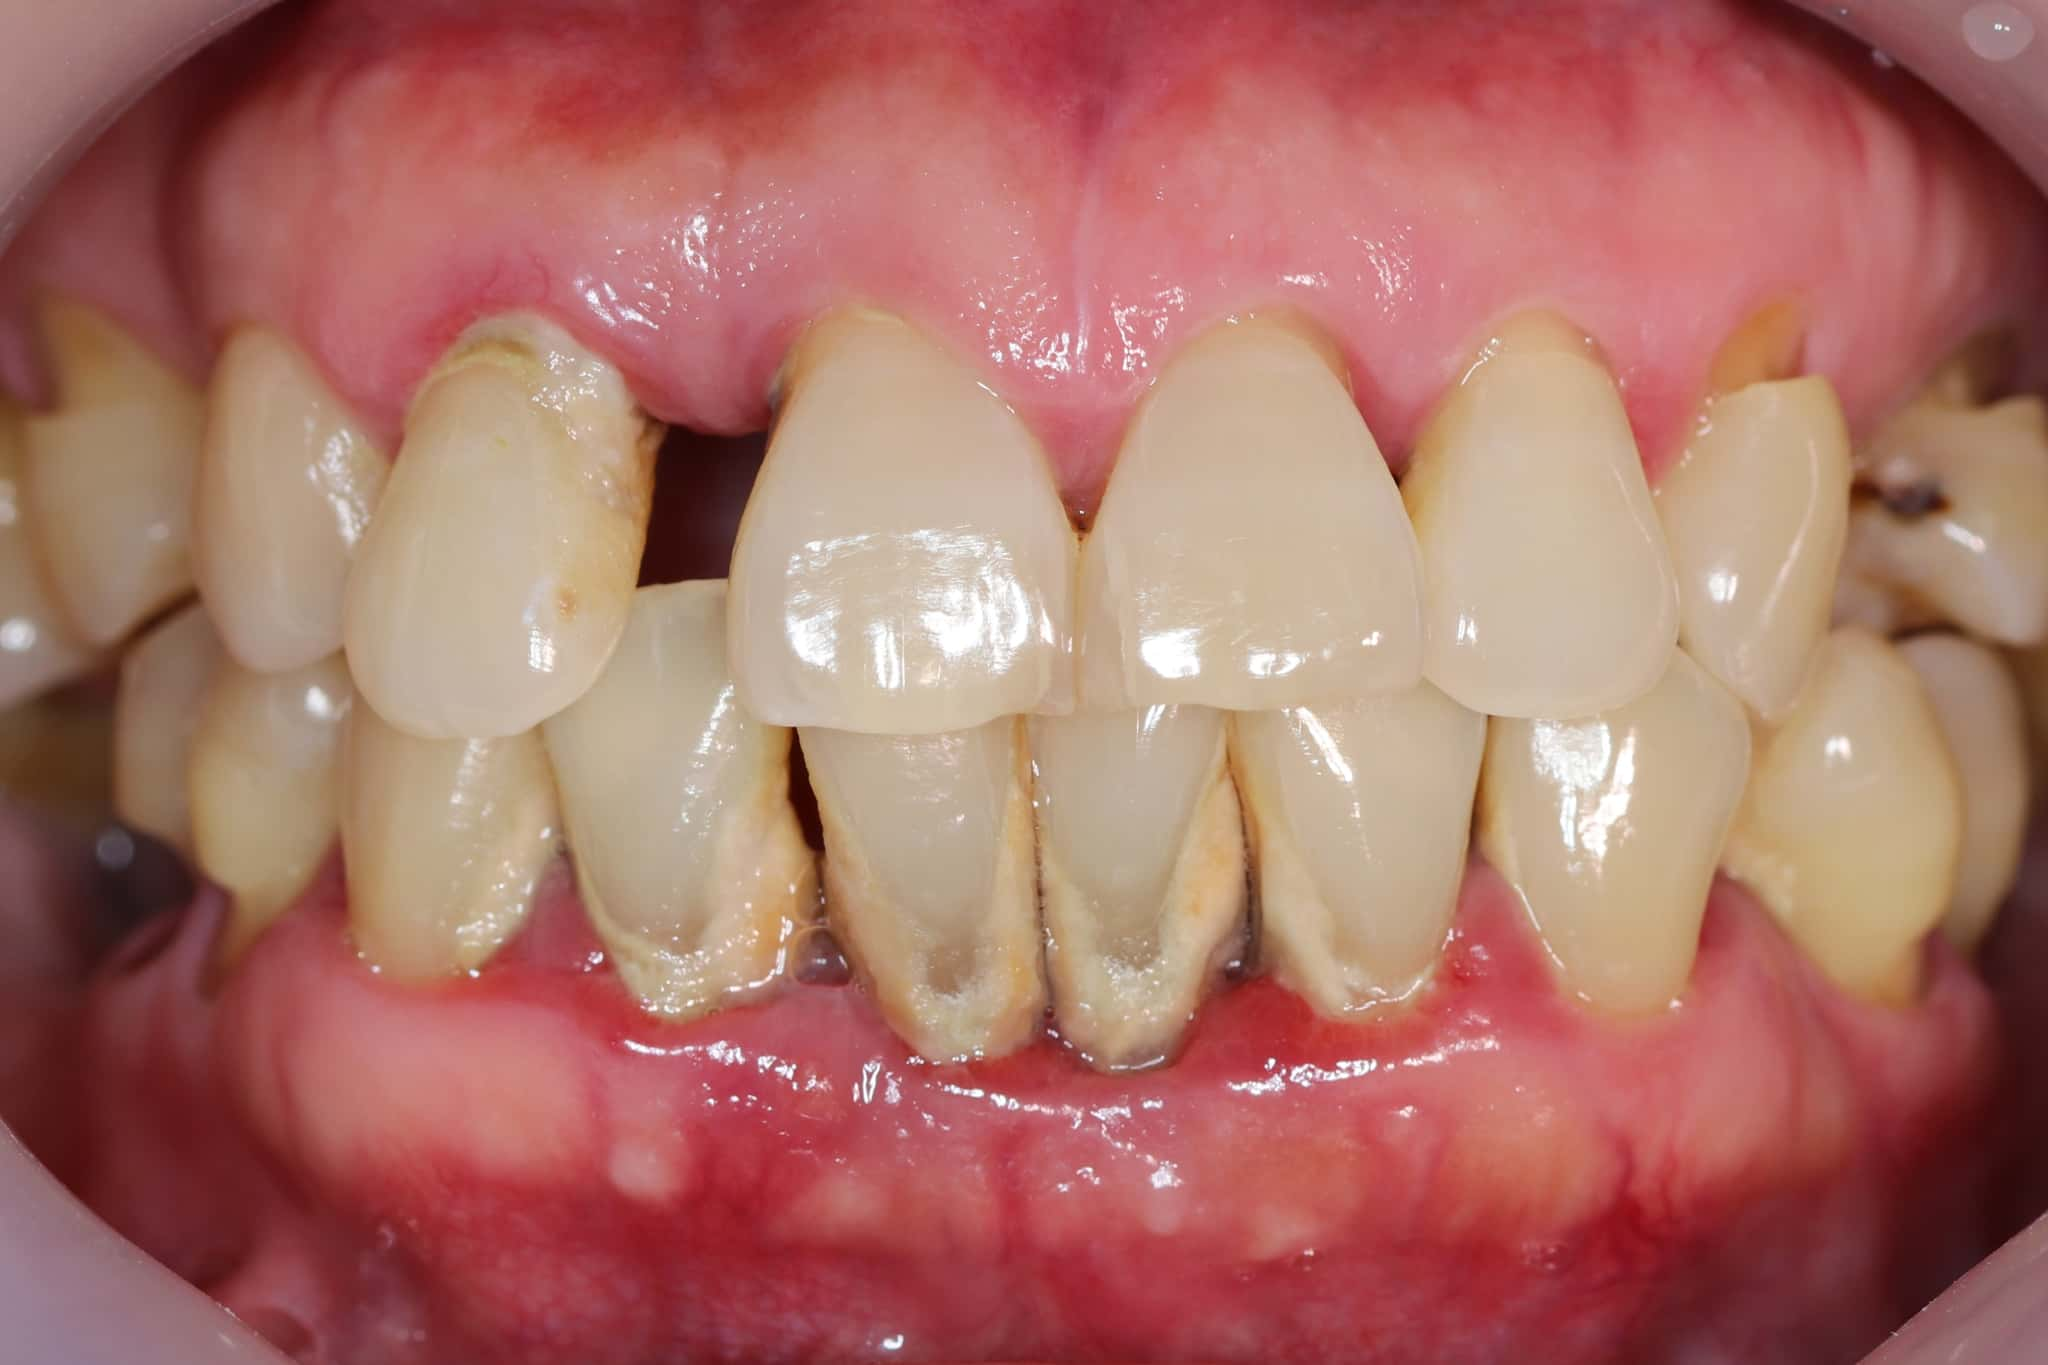

歯周外科治療とは、歯周病が進行し、通常の歯周病治療だけでは十分な改善が難しい場合に行われる外科的な治療です。歯茎や歯を支える骨の状態を直接確認しながら処置を行い、歯周病の進行を抑え、歯をできるだけ長く保つことを目指します。

歯周病は、歯を支えている歯茎や骨が少しずつ破壊されていく病気です。初期の段階であれば、歯石除去やブラッシング指導といった基本的な治療によって改善が期待できます。

しかし、進行すると歯周ポケット(歯と歯茎の間の溝)が深くなり、歯ブラシや通常の治療器具が届かない部分が生じます。そうした場所に歯石や細菌が残り続けると、きちんとケアしていても炎症がなかなか治まらず、症状が長引くことになります。

歯周外科治療は、歯石除去やルートプレーニングなどの基本治療を行っても、十分な改善が得られず、歯周ポケットが深いまま残っているケースで検討されます。さらに、歯槽骨(歯を支える骨)の吸収が進んでいるケース、歯茎の形態に問題があり清掃が難しいケースも適応となります。